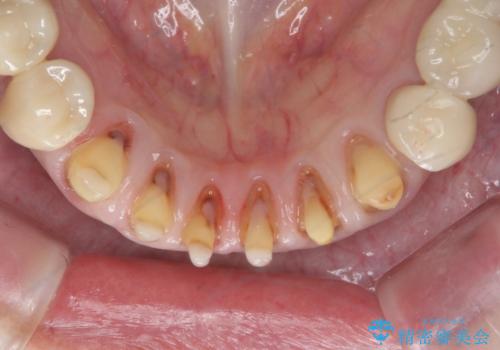

充填されていたコンポジットレジン・小さな虫歯を丁寧に全て取り除いたのち、歯全体を覆い虫歯の再発予防を期待できるセラミッククラウンで補綴を行います。

- 66万円(仮歯・ジルコニアクラウン×6)費用は治療当時の料金となります

コンポジットレジン修復は小さな虫歯を除去したのちの充填には向きますが、充填箇所が複数になってくると審美障害や虫歯の再発リスクが高まります。